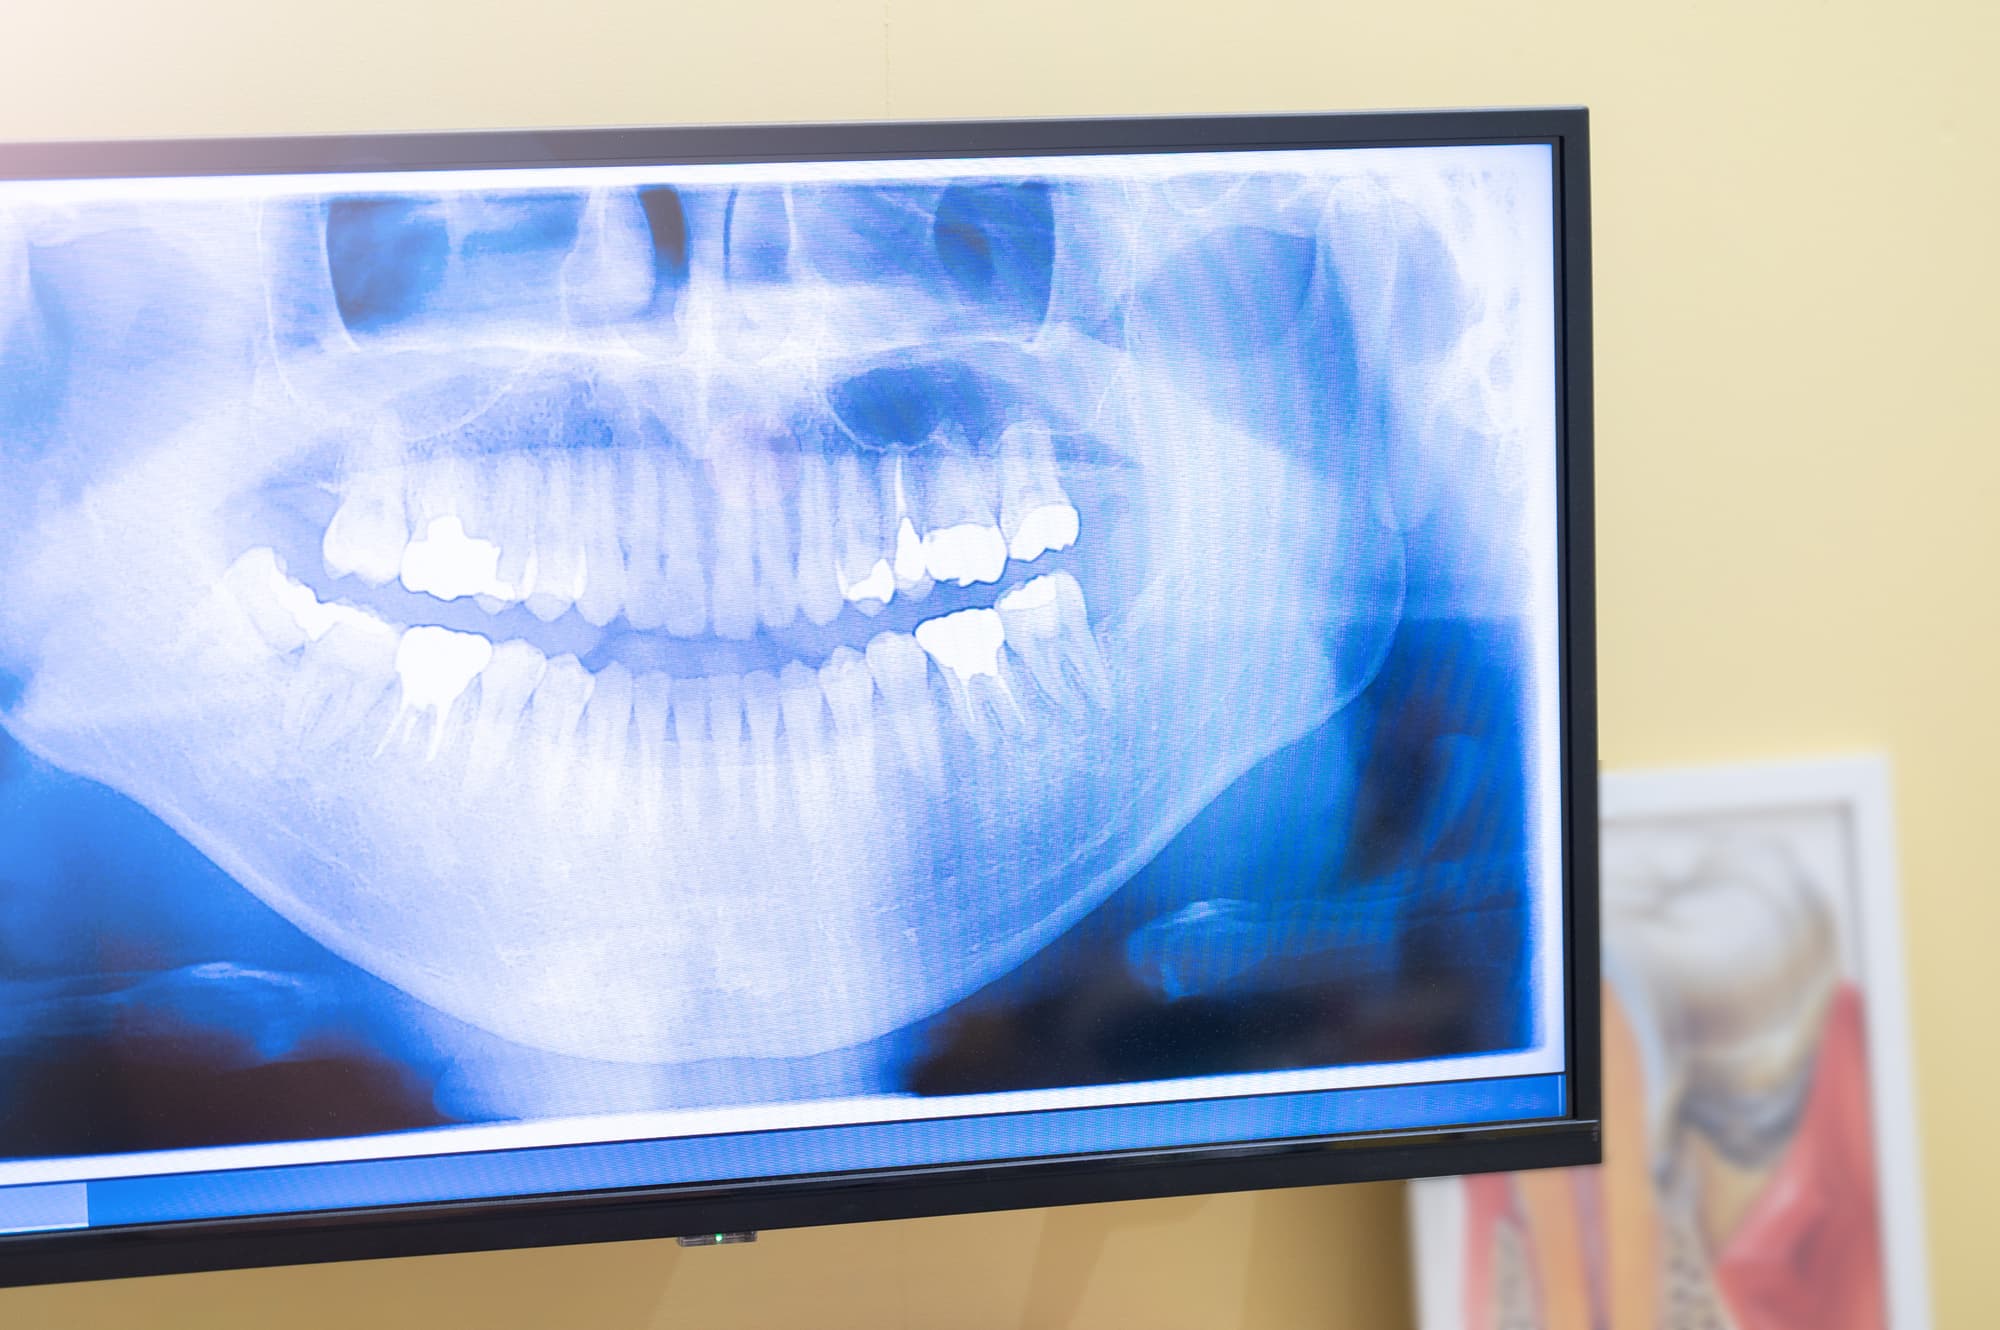

歯科医院のレントゲン検査

治療内容によって通院の回数や期間は変わります。ここでは、初診から治療完了までの流れやおおよその期間について説明します。

1. レントゲン撮影・診断

初診では、レントゲンや視診によって虫歯の進行度を確認します。歯の内部や根の状態を調べ、最適な治療方針を決めていきます。